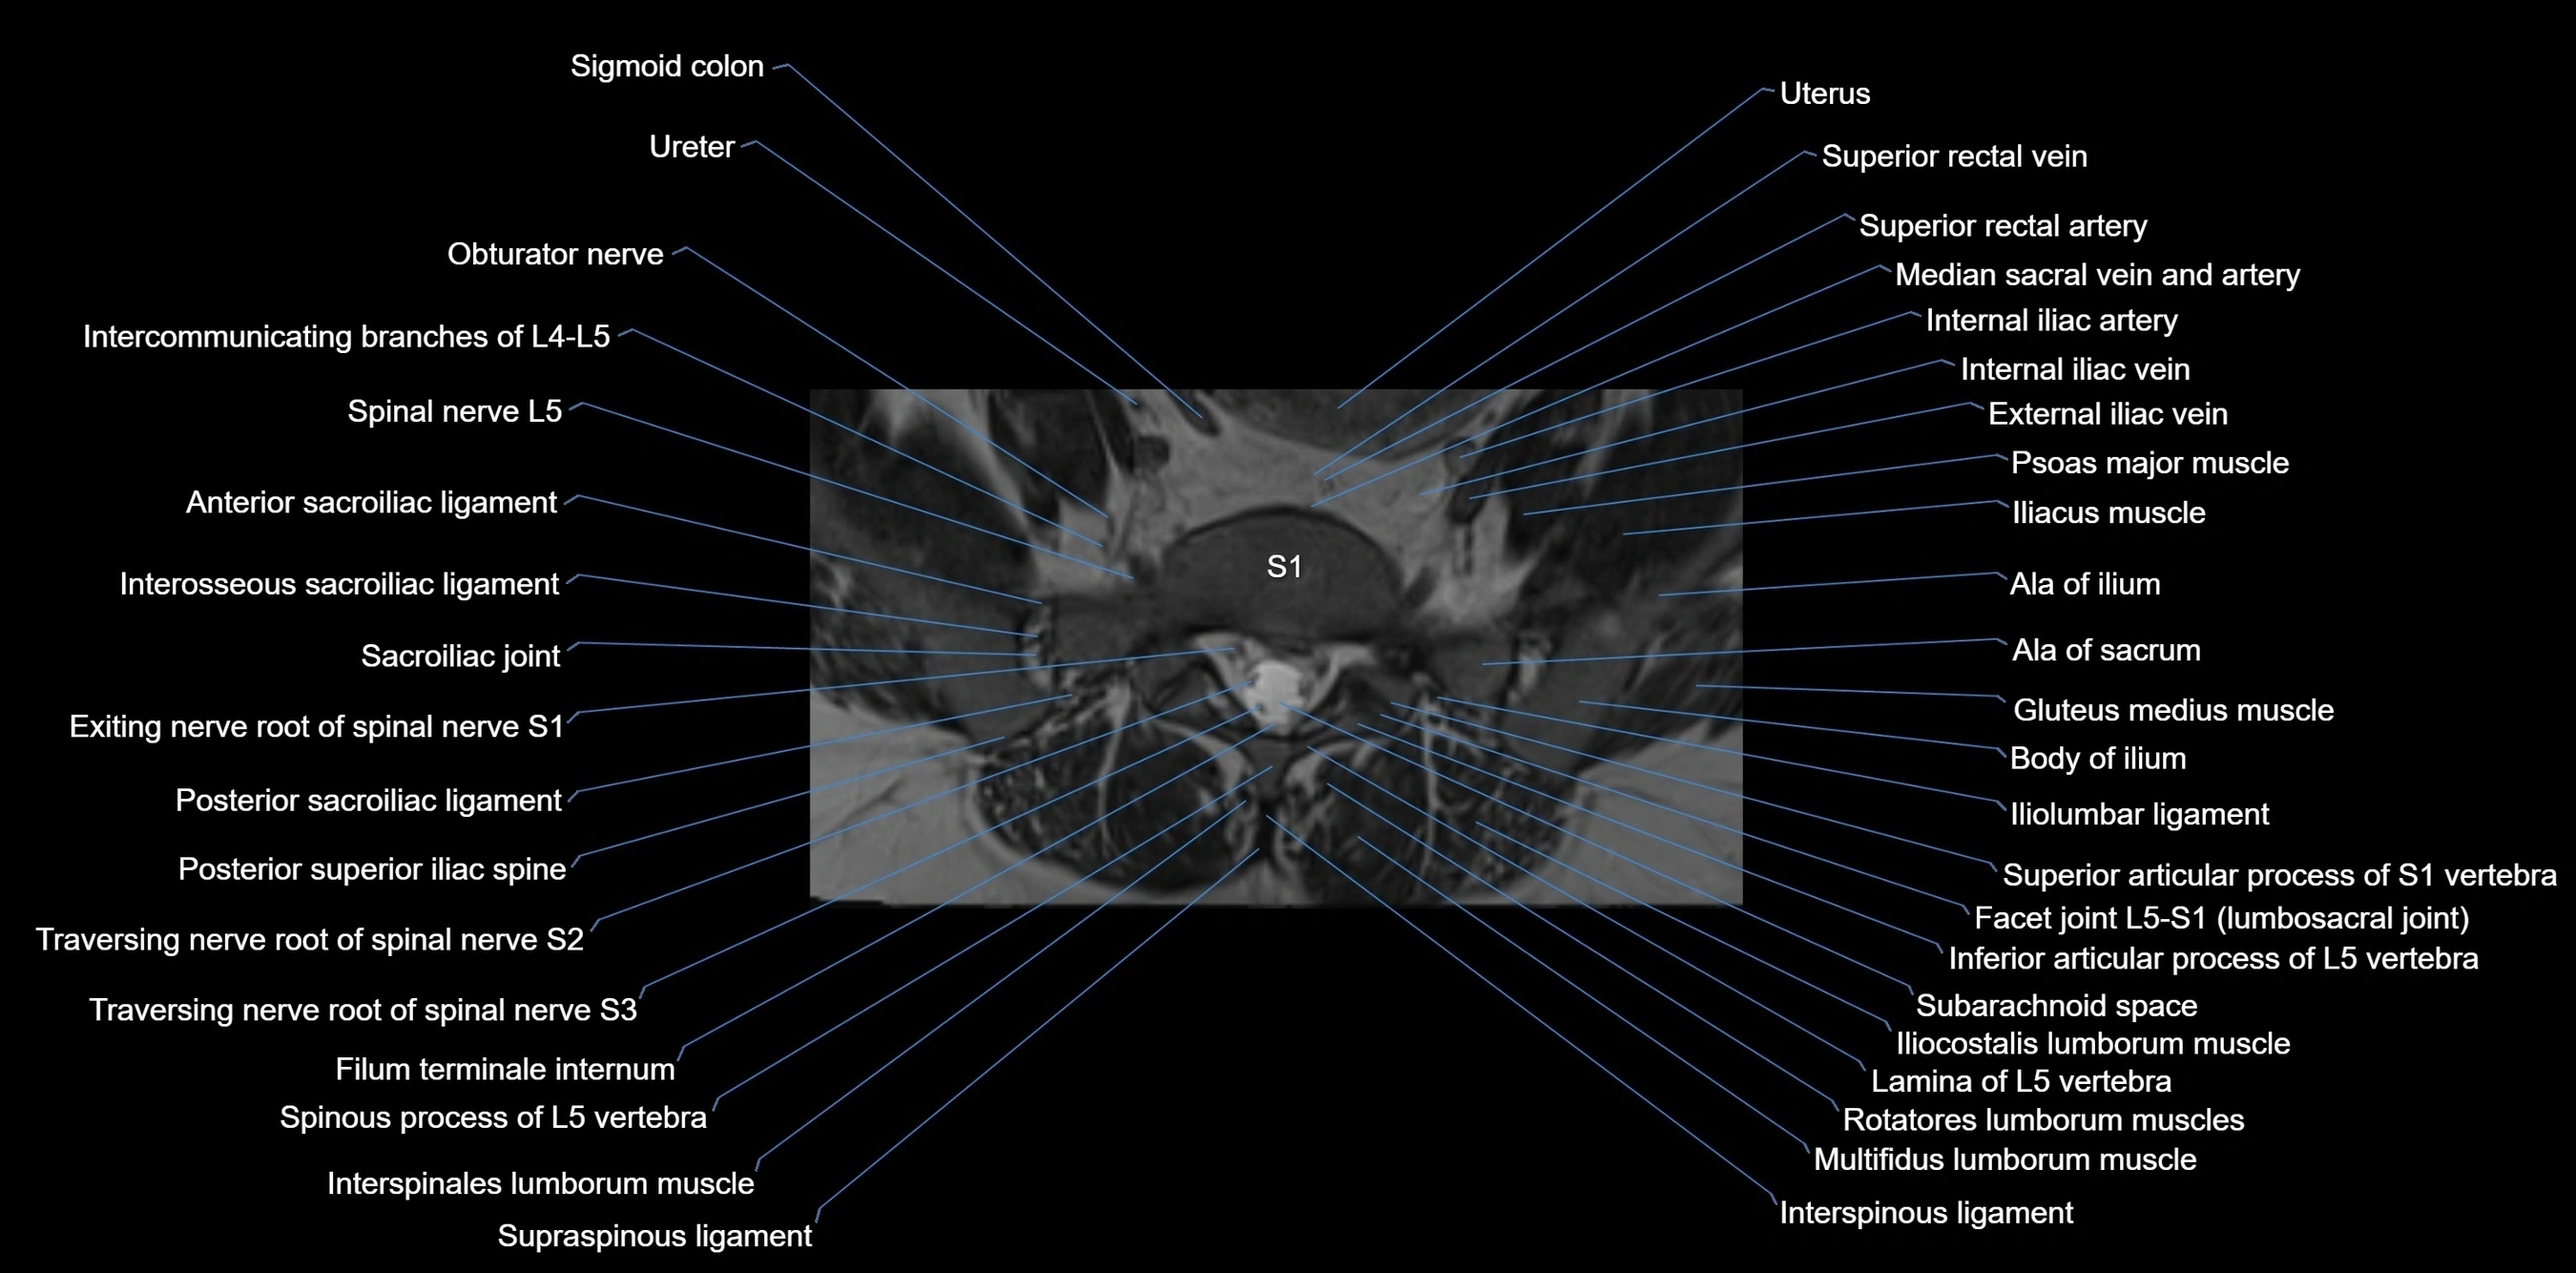

MRI image

image